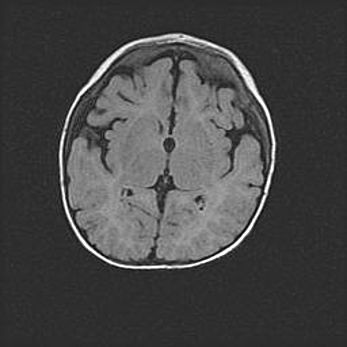

Церебральная ишемия II.

Возраст: 7 дней

Вес: 3350 г

Пол: женский

Окружность головы: 35 см

Срок гестации: 39 недель

Ишемия головного мозга – это состояние, которое развивается в ответ на кислородное голодание вследствие недостаточного мозгового кровообращения. У новорожденных она является следствием дефицита кислорода, что ведет к метаболическим расстройствам различной степени тяжести в тканях головного мозга, в том числе к развитию коагуляционных некрозов и гибели нейронов.